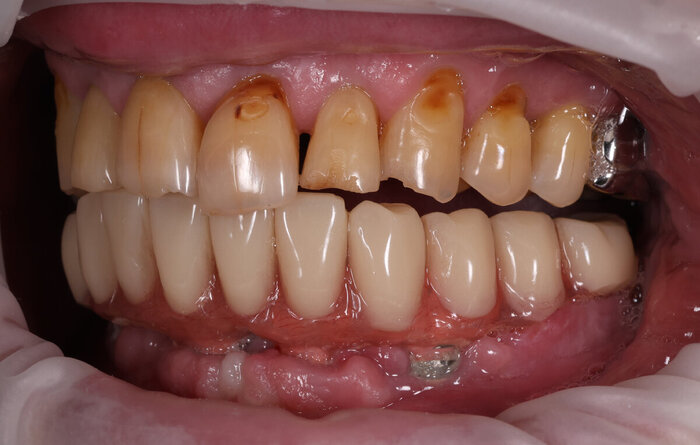

Делаем фото до:

И во рту:

Посмотрим, что во рту:

Временный адаптационный протез с опорой на 6 имплантов. Нижняя челюсть.

До.

До имплантации.

А вот что стало после.